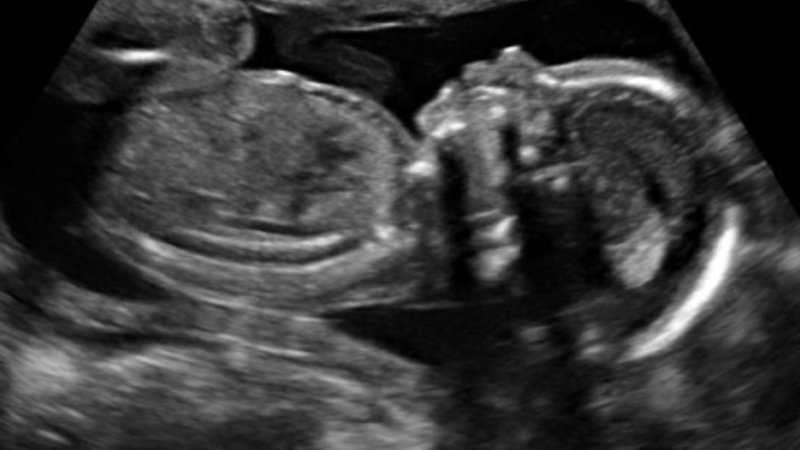

Medlem af Europa-Parlamentet Carlos Salvador mener, at kvinder, der overvejer abort, skal tvinges til at se billeder fra den første scanning af fosteret. Først derefter kan de få tilladelse til provokeret abort.

Skal se første scanning

Abortansøgeren skal nemlig modtage en forseglet kuvert med et billeder fra den første fosterscanning, oplysninger om støttenetværk og onformationer om, hvad en abort egentlig indebærer.

Salvador mener, at det vil få kvinderne til at tænke på fosteret som et levende væsen og ikke som en ”ting, der kan forsvinde ved et trylleslag”.